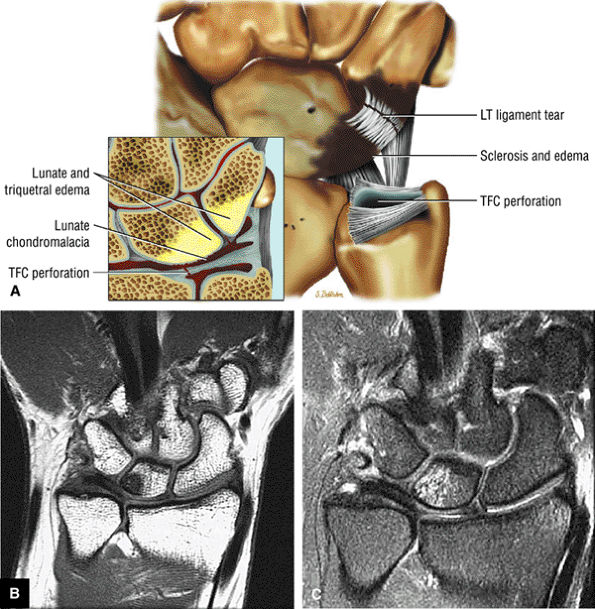

ulnar styloid can chronically impact the proximal triquetrum.